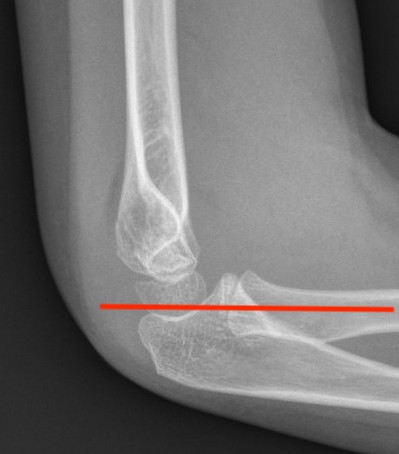

Lateral Xray

Position for good lateral

- thumb vertical

- hand above elbow

Anterior angulation

- shaft - condylar axis

- normally 40o

Lines

Anterior humeral line (AHL)

- should pass through middle of capitellum

Radio-capitellar line

- pass through capitellum

Teardrop

- shadow above the capitellum

- anterior dense line: posterior margin of the coronoid fossa

- posterior dense line: anterior margin of the olecranon fossa

- inferior portion: ossification center of the capitellum